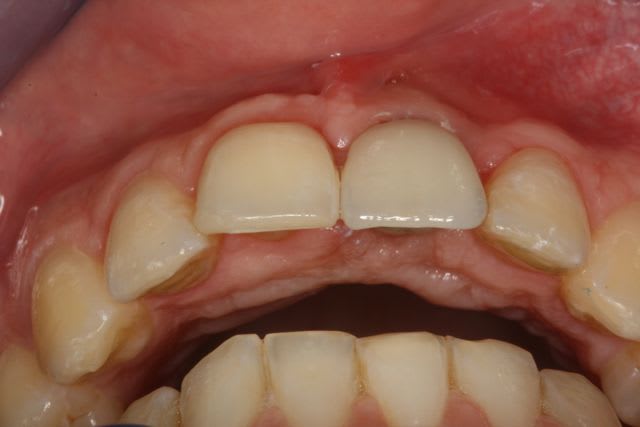

15j après essayage pilier et biscuit, visite au labo pour "finition en bouche" et 3 h après scellement.

le liseré visible en cervicale n'est pas le pilier mais le petit suintement dut à la sonde pour enlever les excès de ciment

Par contre une petite remarque pourquoi avoir fait une couronne aussi triangulaire? Accentuer le coté rectangulaire aurait permis une formation et un maintien plus facile de la papille distale. De plus cela aurait plus symétrique. Donc plus esthétique.

pour la forme de la couronne c'est vrai, je suis 100% d'accord.

Mais comme le patient ne découvre pas, c'est pas trop important pour lui.

Malgré la 'finition au labo' le glaçage est trop marqué, ce qui rend la dent un peu trop brillante par rapport au autre d'ou l'aspect chouilla trop neuf. mais a part nous avec nos yeux trop exigent qui le voit ?